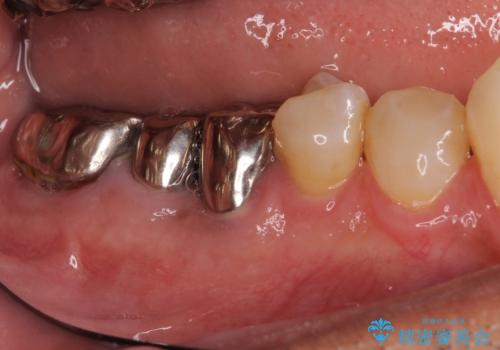

折れてしまった奥歯 インプラントによる補綴治療

診査の結果、5本の奥歯を抜歯してインプラントによる補綴治療が必要と診断されました。

左上の奥歯は2本抜歯が必要であったため、治療期間中は右側に負担がかかり、頻繁に仮歯が壊れてしまいました。

左上に仮歯が装着されたからは咬み合わせが安定し、スムーズに治療を進めることができました。